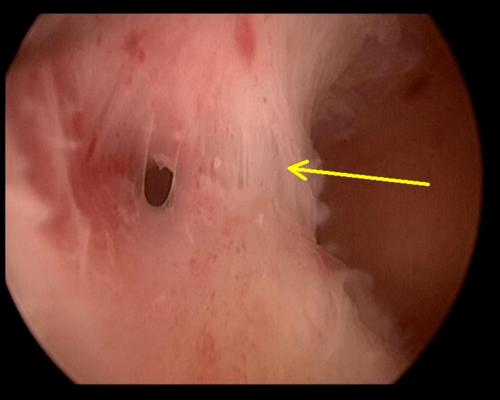

宫腔粘连图片宫腔镜

宫腔粘连图片宫腔镜,宫腔粘连严重图片

宫腔粘连

宫腔粘连宫腔镜

宫腔粘连高清图片